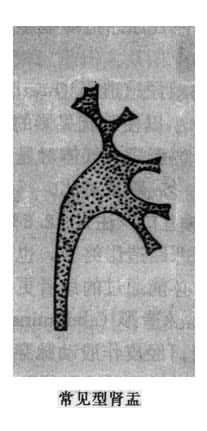

肾小盏分为体部及穹窿部。顶端由于乳头的突入而呈杯口状凹陷,边缘整齐,杯口的两缘为尖锐的小盏穹窿。肾小盏位于不同平面且指向不同方向(主要指向外方),如果肾小盏恰好面向X线束,成横断面投影(或称正位投影),则形成一个环状影或圆形致密影,勿误诊为结石。有时一个肾小盏可接受多个乳头伸入而表现为较大且不规则,多见于上、下盏。肾小盏体部较窄,又称为漏斗部。肾大盏边缘光滑整齐,略成长管状,可分三部:①顶端或尖部,与数个肾小盏相连;②峡部或颈部,即为和长管状部;③基底部,与肾盂相连。肾大小盏的形状和数目变异较多,有的粗短,有的细长,两侧肾盏的形状、数目亦常不同。但一般肾大盏常为3个。肾盂多位于第二腰椎水平,略呈三角形,上缘隆凸,下缘微凹,均光滑整齐。肾盂开头亦有较大变异,多呈喇叭状,少数可呈分支状,即肾盂几乎被两个长形肾大盏所代替。有的肾盂呈壶腹形,直接与肾小盏相连而没有肾大盏。这种肾盂勿误诊为肾盂扩大。肾盏和肾盂均有蠕动,有时其边缘可见到暂时性凹陷或狭窄,为蠕动波所成。肾血管有时亦在肾盏或肾盂边缘造成小的压迹,均属正常(图4-4-1)。

图4-4-1 正常肾盂肾盏不同形状(虚线状代表肾的内缘和肾门区)